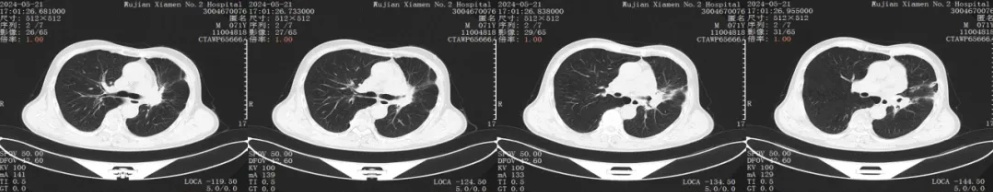

后续治疗:目前共进行了50周期的免疫治疗,病情稳定,建议给予停用

胸部CT平扫+增强:2025年2月20日末次用药,停用4月后复查

疗效评价:SD(近期于2025年6月16日复查CT,复查结果显示病情稳定)